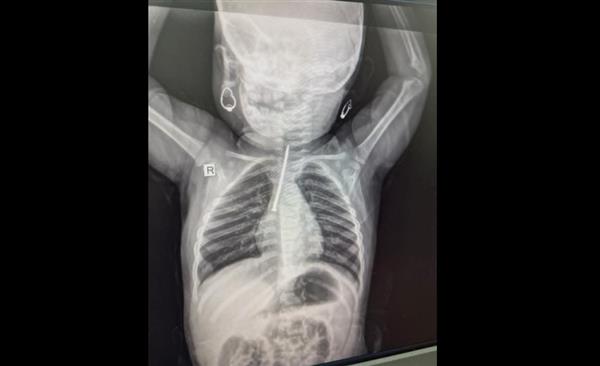

نجح أطباء في إنقاذ حياة رضيعة عراقية تبلغ من العمر عشرة أشهر، بعد أن ابتلعت مسمارًا استقر في قصبتها الهوائية.

وبحسب وسائل إعلام محلية، كانت الطفلة قد وصلت إلى مستشفى السلام في الموصل بعد أن ابتلعت جسمًا غريبًا، فيما تمكن فريق طبي بقيادة الدكتور محمد سالم المشهداني، اختصاصي جراحة الصدر والقلب والأوعية الدموية في محافظة نينوى، من إزالة مسمار طويل باستخدام منظار القصبات الهوائية، في عملية دقيقة أُجريت عند الساعة الحادية عشر ليلًا.